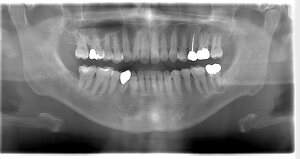

レントゲン写真

- 透過像

症例写真-1

- Befor

- After

症例写真-2

- 途中経過

| 年齢 | 50代・男性 |

|---|---|

| 主訴 | 右下歯が疼く |

| 治療内容 | ・右下6番インプラント ※1:FGG(遊離歯肉移植術)とは、足りない歯ぐきを上顎から上皮を切り取り移植する外科手術 |

| 治療費 | 合計:902,000円(税込) ■内訳 |

| 治療期間 | 9ヵ月 |

| 治療方針 | 右下の当該歯は歯根破折により保存不可能と診断しました。歯周疾患も伴っていたため抜歯後に骨吸収※1が大きく起こることが予測できました。チタンメッシュ併用骨再生誘導法(GBR※2)を選択しインプラント埋入と同時に行い自然な歯槽骨のラインを再現しました。またGBRを行う際にインプラント辺縁の付着歯肉の減少が起こる為、遊離歯肉移植術(FGG※3)を行い清掃性を考慮した形態に仕上げました。 ■治療方針の解説 治療した右下の歯をレントゲンで撮影したところ根本の部分に黒く写る箇所があり「根尖性慢性周囲炎※1」と診断。また歯周病も進行していました。 ※1 骨吸収・・・歯槽骨という歯を支える骨がなくなっていくこと |

| 担当者所見 | 主訴の右下だけでなく歯茎の腫れ、発赤があり不良補綴や不良充填など他にも治療箇所が多数ありました。プラークコントロールが不良であった為まずはブラッシング指導を行いセルフケアの重要性を理解していただくところからスタートしました。 右下6番の歯はインプラント治療を行なった結果審美的にも機能的にも患者様の満足を得ることができました。骨造成と歯肉移植も行なった為インプラントを支える十分な歯周組織の獲得ができたと思っております。 |